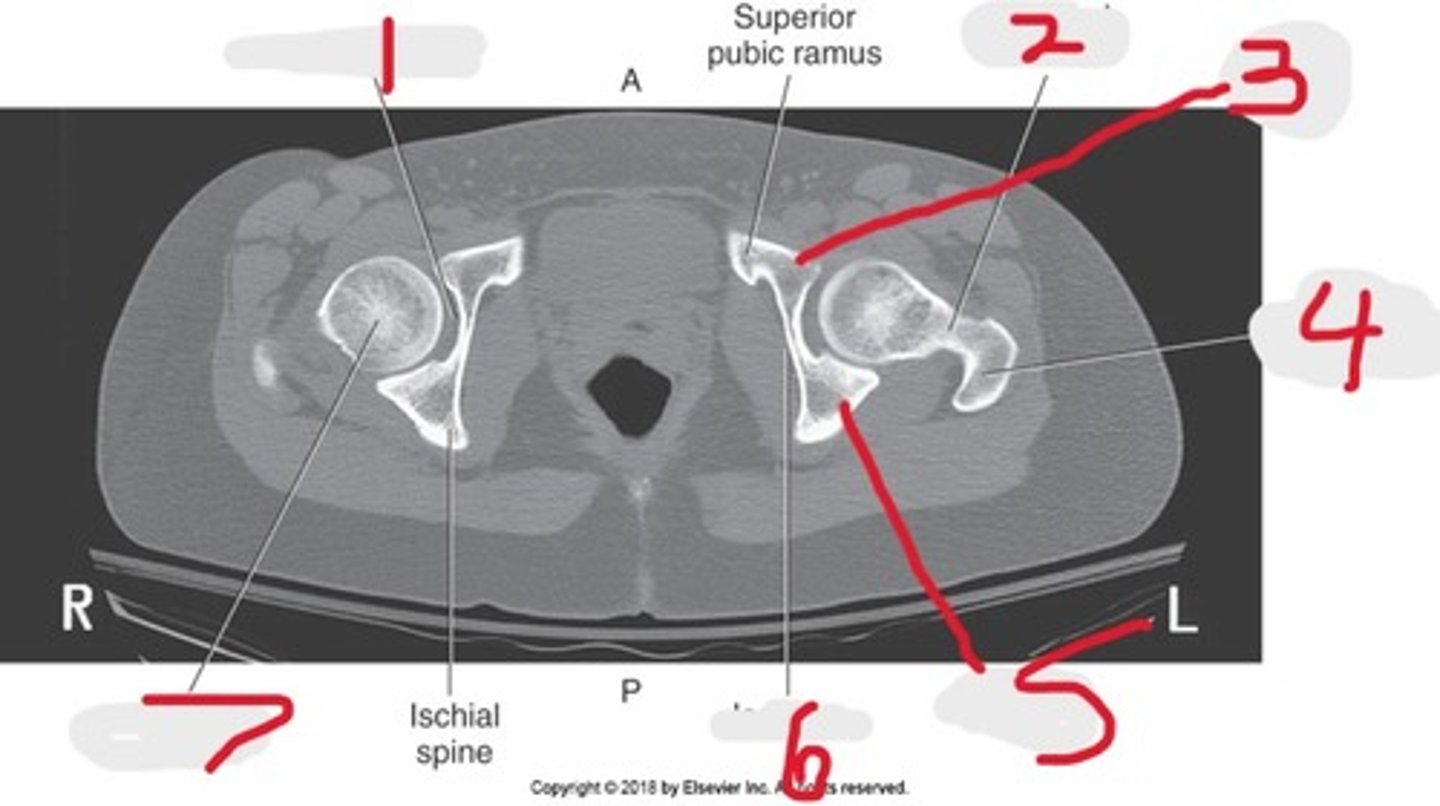

1) Iliac crest

2) Ilium

3) Acetabulum

4) Pubic symphysis

5) Ischium

6) Coccyx

7) Ala of ilium

8) Lateral mass (ala)

9) Sacrum

10) SI joints

Name all numbered structures

1) SI joint

2) Body

3) Sacral promontory

4) Sacral canal

5) Ilium

6) Lateral mass

7) Articular process

Name all numbered structures